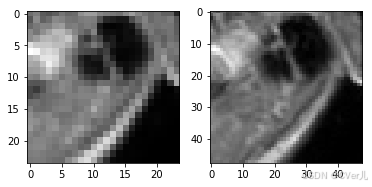

if __name__ == '__main__':

test_dataset = MyDataset(mode='train')

lr,hr = test_dataset[0]

print(np.array(lr).min(),np.array(lr).max())

print(np.array(hr).min(),np.array(hr).max())

plt.subplot(1,2,1)

plt.imshow(lr[0],cmap='gray')

plt.subplot(1,2,2)

plt.imshow(hr[0],cmap='gray')

plt.show()

0.0 1.0 0.0 1.0

<Figure size 432x288 with 2 Axes>